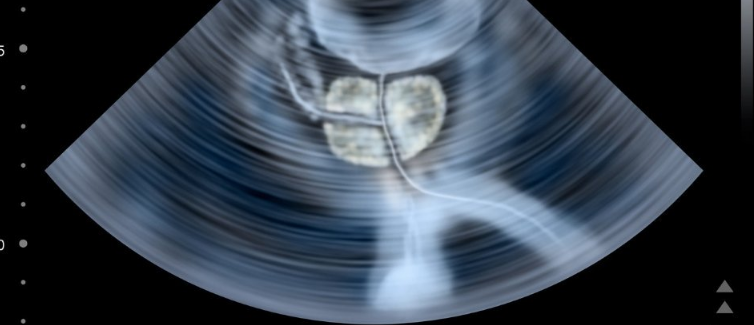

PSA测试是使用少量血液来检测前列腺特异性抗原(PSA)的水平升高来完成。然而,尽管其成本相对较低且易于管理,但在包括英国在内的许多国家/地区仍未将其用于常规筛查。